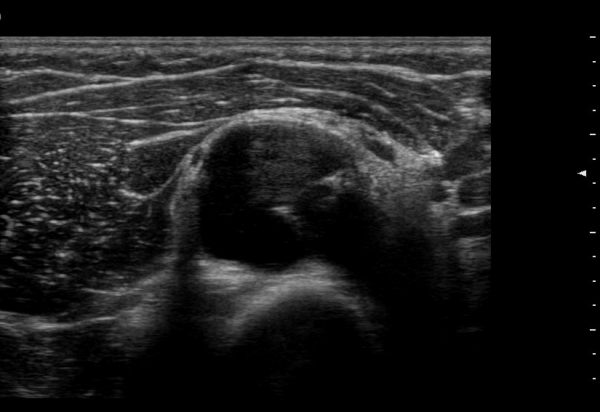

ŽÃËÀÚ¸¦ ¸»´ÜÀ¸·Î À̵¿ÇÏ´Ï ¿ä°ñµÎ ºÎÀ§¿¡¼­ Àú¿¡ÄÚ ³¶Á¾ÀÌ Èİñ°£½Å°æºÐÁö¸¦ Ç¥ÃþÀ¸·Î

ÀüÀ§½Ã۰í ÀÖ´Ù(±×¸² 2, 3,)